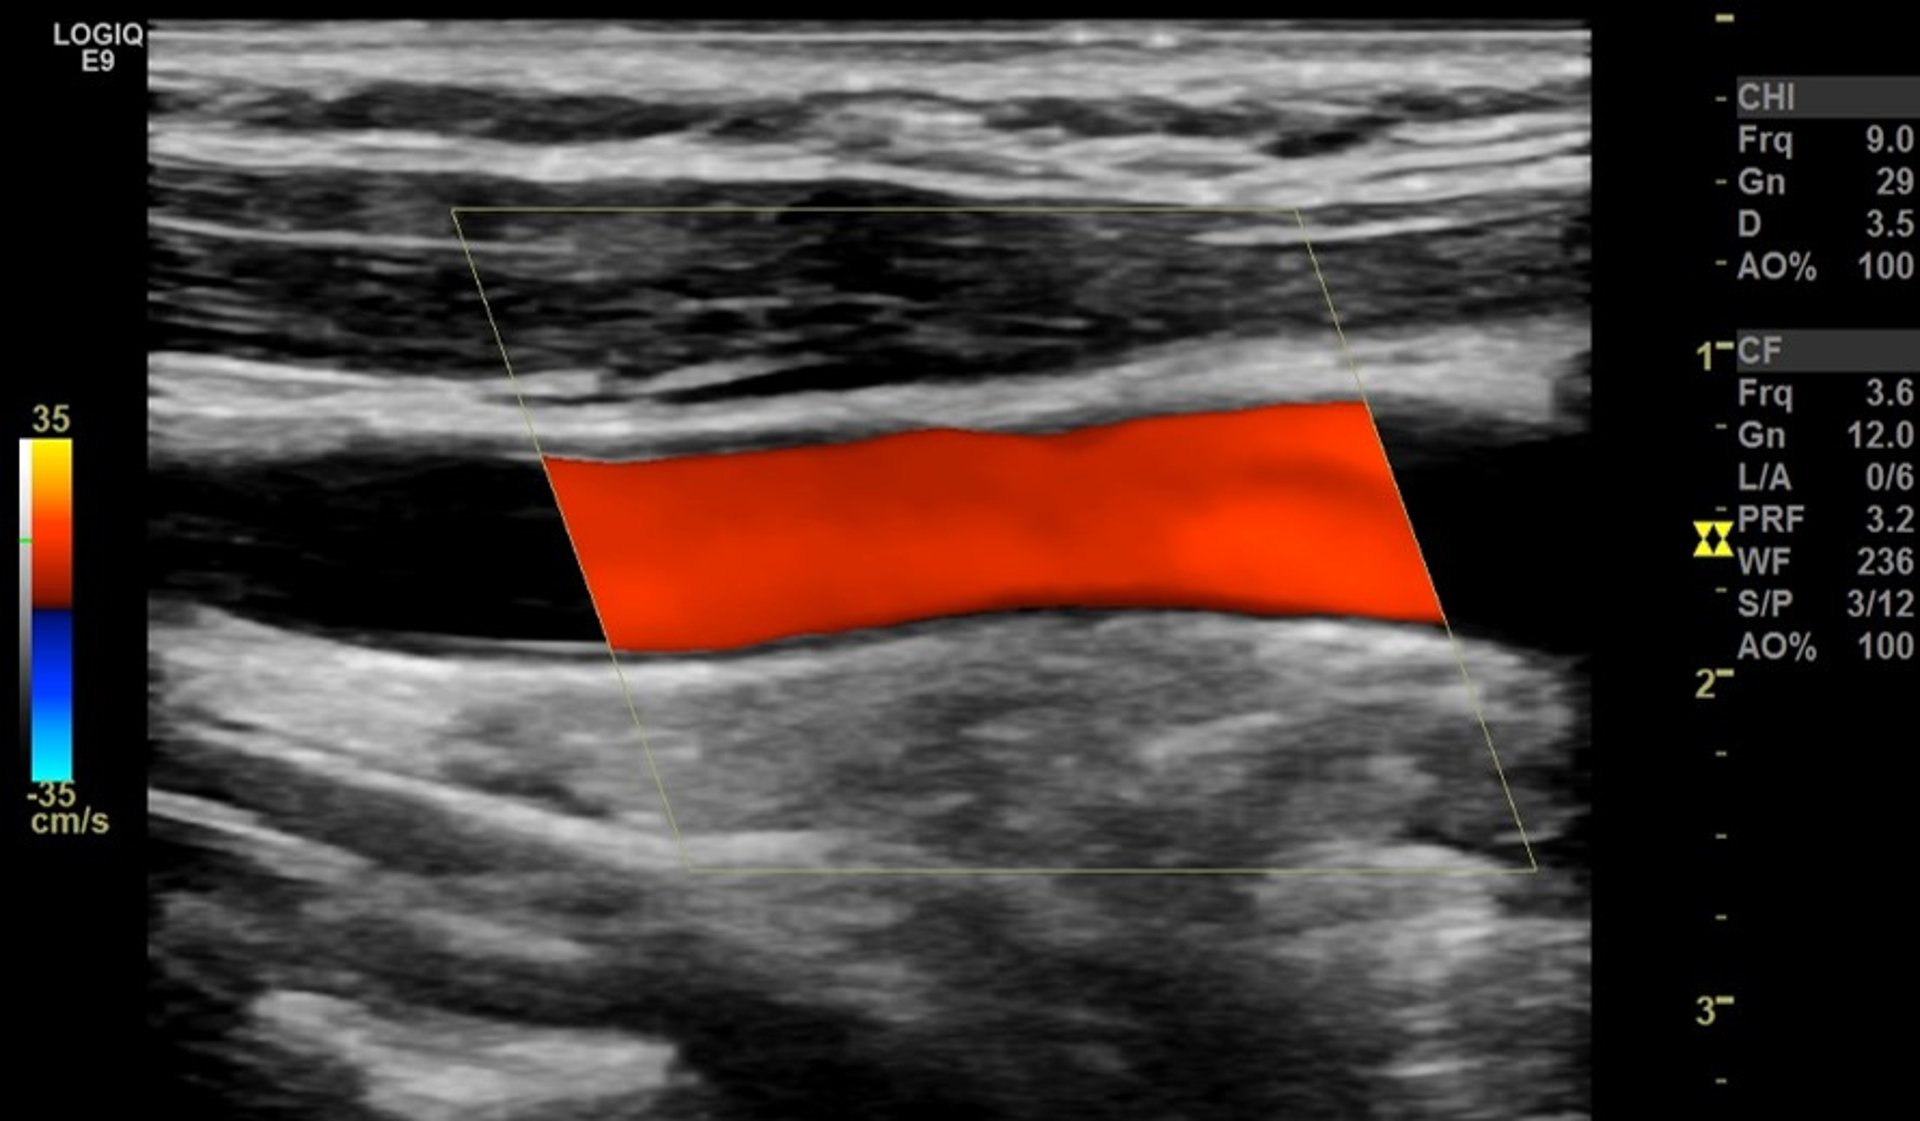

Ultrassonografia com Doppler colorido da artéria carótida

A faixa vermelha representa o fluxo sanguíneo normal e desobstruído passando através de uma grande artéria no pescoço (artéria carótida comum), visualizada pela lateral.

Imagem fornecida pelo Dr. Mustafa Mafraji